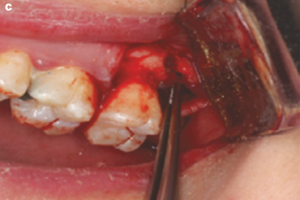

Рис. 1. Конусно-лучевая компьютерная томограмма пациентки С.: зубы 1.6 (а) и 2.8 (б)